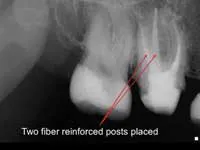

Less than one-half of the coronal tooth structure remaining (Figs. 1-6)

It is my opinion, regardless of the other factors present, that it is still advisable to place a post or posts in such teeth. Endodontically treated teeth with less than one-half of the coronal tooth structure remaining have a reduced chance of long-term service, and patients should be so advised as the treatment plan is developed.